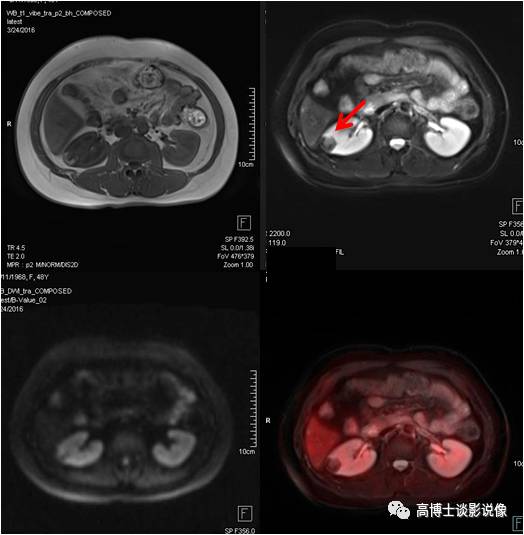

肾上腺腺瘤

中年男性,无任何症状。左侧肾上腺结合部见一长径约1.8cm结节,FDG稍摄取,考虑为肾上腺腺瘤。

点评

根据是否有功能,可分为无功能性和功能性腺瘤。一般来说,偶然发现的肾上腺腺瘤都是无功能性的。对于无功能性腺瘤,注意定期复查。功能性腺瘤需要专科医生进行评估,最好是具备诊断肾上腺肿瘤丰富经验的放射科医师、内分泌医生和外科医生组成的评估小组。

髓样(质)脂肪瘤

中年女性,左侧肾上腺见一大小约1.9cm×2.1cm的类圆形异常信号灶,信号不均匀,内含脂肪信号,考虑为髓样脂肪瘤。

点评:

本病很少出现临床症状,多在体检时偶然发现。如肿瘤较大压迫邻近组织器官或瘤内出血坏死,可引起不适症状。但对于直径较小且无临床症状者应随访观察。